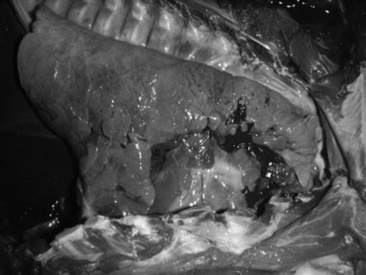

Grossly, lungs of cattle with pneumonia caused by Mycoplasma bovis have dark red, firm consolidated lobules of the cranioventral lung. Raised white to yellow, firm nodules that range from 0.5 to several centimeters in diameter are often but not invariably seen clustering in the cranioventral lung (Figs. 31-60 and 31-61).357,364,379,385 These nodules may appear to be abscesses, but in most cases they are actually foci of coagulation necrosis.357,379 Differential diagnoses for gross lesions of abscessing pneumonia in cattle include infection with Arcanobacterium (Actinomyces) pyogenes and F. necrophorum (both of which are more likely to cause a foul odor than Mycoplasma bovis) and Mycobacterium bovis (tuberculosis).364 Other gross lesions include enlargement of interlobular septa by edema and fibrin; fibrinous or fibrous pleural adhesions are unusual but could be present if the animal is or has been co-infected with M. haemolytica or H. somnus. Animals with pneumonia typical of Mycoplasma bovis may also have arthritis in one or more joints characterized by abundant yellow fluid with fibrin and sometimes purulent material, and tenosynovitis characterized by extensive caseous exudate and pyogranuloma formation in the tendon sheaths.362,364 Fibrin, purulent material, and caseous material may be present in the tympanic bullae.

Fig. 31-60 Postmortem photograph of lung from calf with bronchopneumonia caused by Mycoplasma bovis. Note extensive nodular abscessation of cranioventral lung.

Photograph contributed by Dr. Tom Mullaney, Michigan State University, East Lansing Mich.